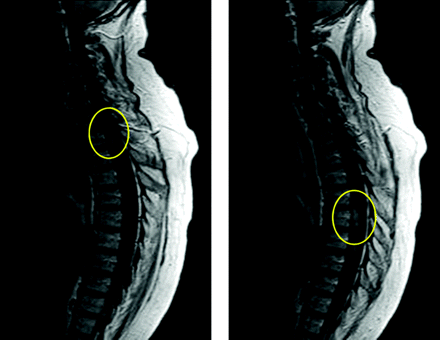

Đề cập đặc biệt nên chẩn đoán cẩn trọng đối với bệnh giun đầu gai thể thần kinh trung ương. Dịch não tủy nếu có sẽ biểu hiện tăng bạch cầu ái toan, kèm theo tăng áp lực và tăng protein. Xét nghiệm huyết thanh học cho mẫu dịch não tủy là không cần thiết và cũng không phải làm thường quy và chưa có ấn bản về dữ liệu như thế. Chụp MRI có ích để chỉ ra hình ảnh tổn thương di chuyển trong tủy sống. Ký sinh trùng làm cho hình ảnh cường độ tín hiệu cao trên T2 và tăng cản quang ở T1, điều này nếu không chuyển động sẽ góp phần và các hình ảnh viêm, mạch máu, khối tân sinh hoặc nhiễm trùng khác. Tuy nhiên, bản chất di chuyển của các thương tổn như vậy sẽ phù hợp với con đường di chuyển của ấu trùng đã trình bày rất tuyệt vời đối với giun Gnathostoma. Xơ hóa đa ổ cũng sẽ sinh ra các tổn thương từng đợt trên hình ảnh chụp cộng hưởng từ, nhưng điều này có thể loại trừ nhờ vào xét nghiệm dải band đơn dòng trong dịch não tủy (CSF oligoclonal bands).